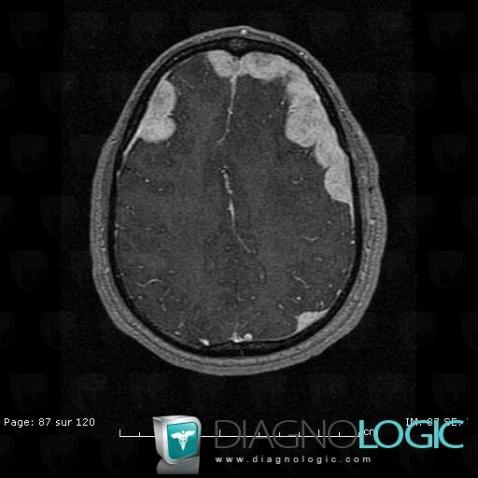

Langerhans cell histiocytosis, Cerebral hemispheres, MRI

Here is the specific information in the key image above:

- Diagnosis Langerhans cell histiocytosis, Location(s) Cerebral hemispheres, with gamuts Intracerebral lesion with intense enhancement